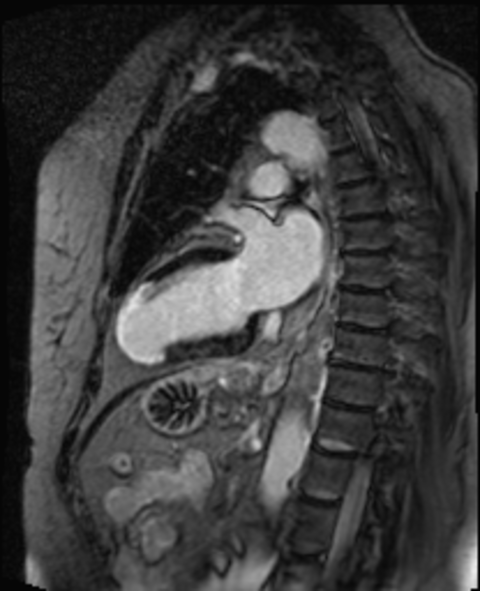

Bei einem Herzinfarkt wird ein Teil des Herzmuskels geschädigt, was zu einer Vernarbung des Herzmuskels in diesem Bereich führt. Mittels kardialer MRT kann eindeutig festgestellt werden, wie weit die Vernarbung fortgeschritten ist und wie viel gesunder Herzmuskel noch zur Verfügung steht. Diese Information ist wichtig zur Planung der weiteren Behandlung des Herzinfarktes zum Beispiel mittels Medikamenten, Herzkatheter oder Bypass-Operation.